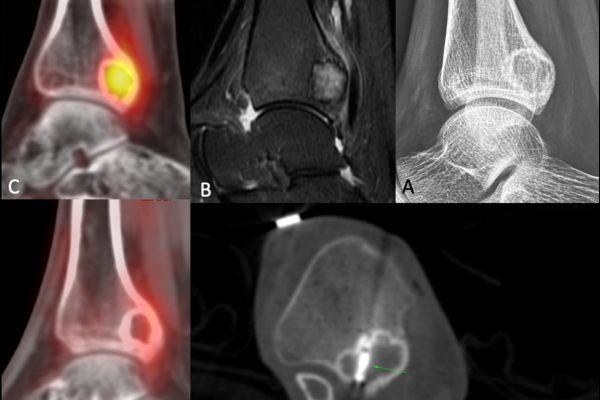

- Cancer Detection: Highlights tumours and measures their size and spread.

- Advanced Technology: Modern equipment that may also be available in the form of a 3D CT scan.

Advances in CT technology keep bringing into play advanced diagnostic capabilities. A notable example is the conception of 3D CT, which, through its clear images, is quite useful for complex cases or, rather, surgical planning.